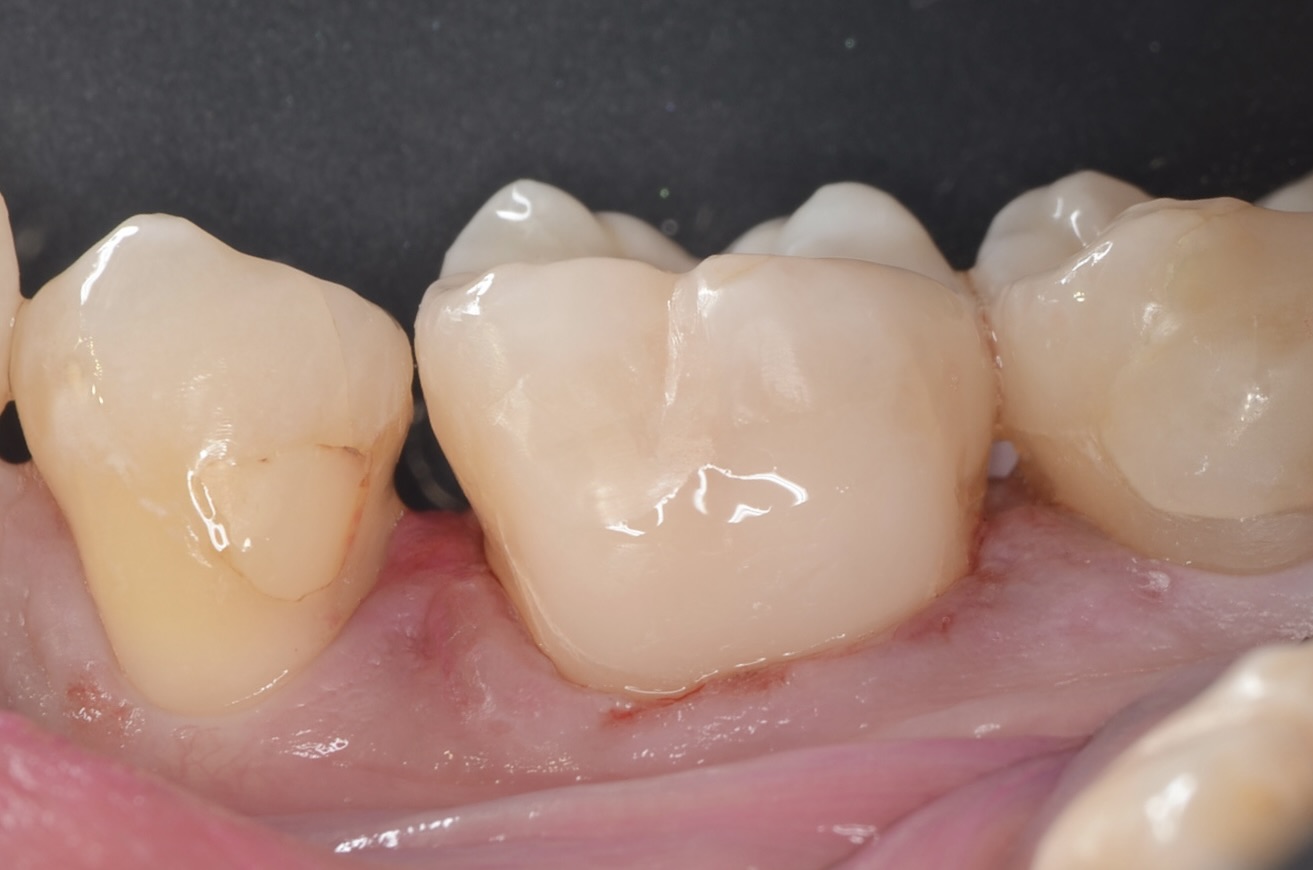

頬側面から見る

滑らかな段差の無い形態で形態に治す事ができました。